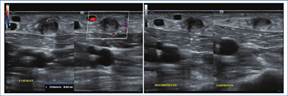

Los hallazgos en la ecografía Doppler (Fig. 1) son:

Directos: reducción del diámetro de la luz > 50% (área transversal del sitio de estenosis comparada con el área transversal de un segmento normal cercano a la estenosis), velocidad pico sistólica (VPS) en el sitio de estenosis > 400 cm/s, ratio VPS estenótica/VPS preestenótica > 3,5, luz permeable < 2 mm1,4,5.

Indirectos: flujo de alta resistencia, reducción en el volumen de flujo del acceso, artefacto de aliasing en la evaluación con Doppler color4,5.